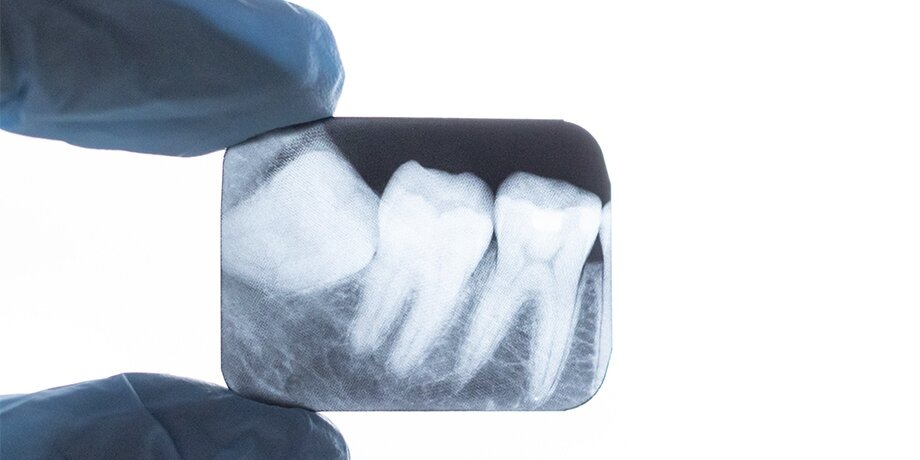

С точки зрения медицинских норм, удаленные зубы подлежат утилизации из-за возможного содержания возбудителей инфекций. Об этом в беседе с Москвой 24 рассказал стоматолог, челюстно-лицевой хирург Олег Бутенко.

"Зуб мудрости представляет уникальный орган, содержащий нервную и мезенхимальную ткани, нервно-сосудистый пучок, а его эмаль является самой твердой тканью в человеческом организме. Благодаря сохранности клеток пульпы, погруженных в дентин и эмаль, зубы в целом могут служить для идентификации личности даже спустя тысячелетия", – отметил он.